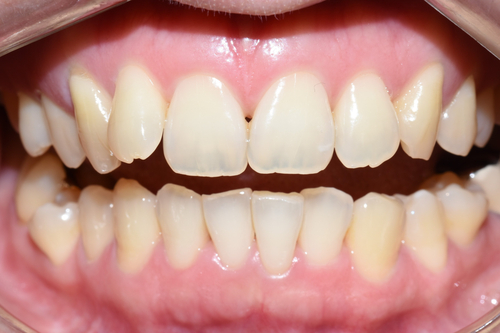

![[시청역/광화문/서대문]삐뚤삐뚤한 치아 무삭제라미네이트로 치아성형 관련 이미지 7](https://pub-9f2bb3498faf4d1d8714b41df24753e3.r2.dev/content/clinics/archive/rseeanjxfu/naver_blog/yonseiyegam/assets/by_hash/4af571c87bde6fa9f3139c67a228689e20519a09c302715b04534d61941cd6b5.jpg)

윗니 라미네이트5개와 크라운 전후 입니다.

윗니 라미네이트5개와 굉장히 많이 튀어나온 치아 1개 크라운으로 자연스럽고 고른 치아가 되었습니다.